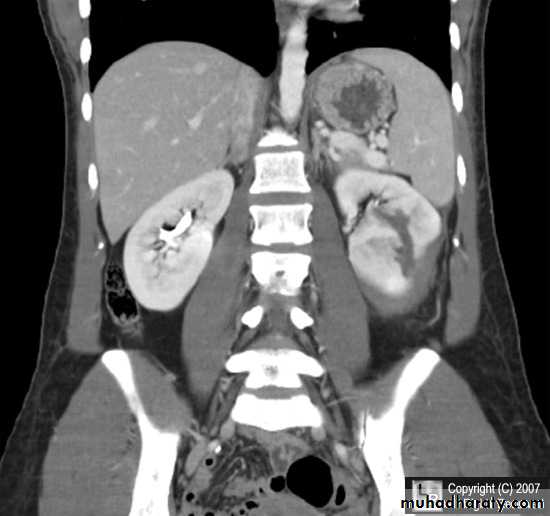

Classification of hydronephrosis in grade I–IV.

• Hydronephrosis grade I: dilatation of the renal pelvis without dilatation of the calices without signs of parenchymal atrophy. • Hydronephrosis grade II: dilatation of the renal pelvis and calices. No signs of parenchymal atrophy. • Hydronephrosis grade III: Minor signs of organ atrophy present (flat papillae and blunt fornices).• Hydronephrosis grade IV: massive dilatation of the renal pelvis and calices. Significant signs of renal atrophy (thin parenchyma).